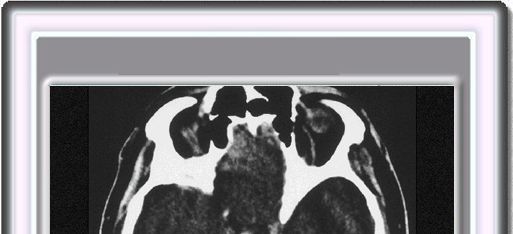

HEMORRAGIA SUBARACNOIDEA

La hemorragia subaracnoidea es un síndrome que tiene lugar como consecuencia de la ruptura de uno o más vasos sanguíneos en el espacio subaracnoideo. Cuando esto ocurre, la sangre irrumpe en el espacio subaracnoideo con una elevada presión y generalmente se manifiesta clínicamente como unas cefalea de gran intensidad, explosiva y aguda, que puede acompañarse o no de una disminución del nivel de conciencia, el cual puede ir desde la simple somnolencia hasta el coma profundo.